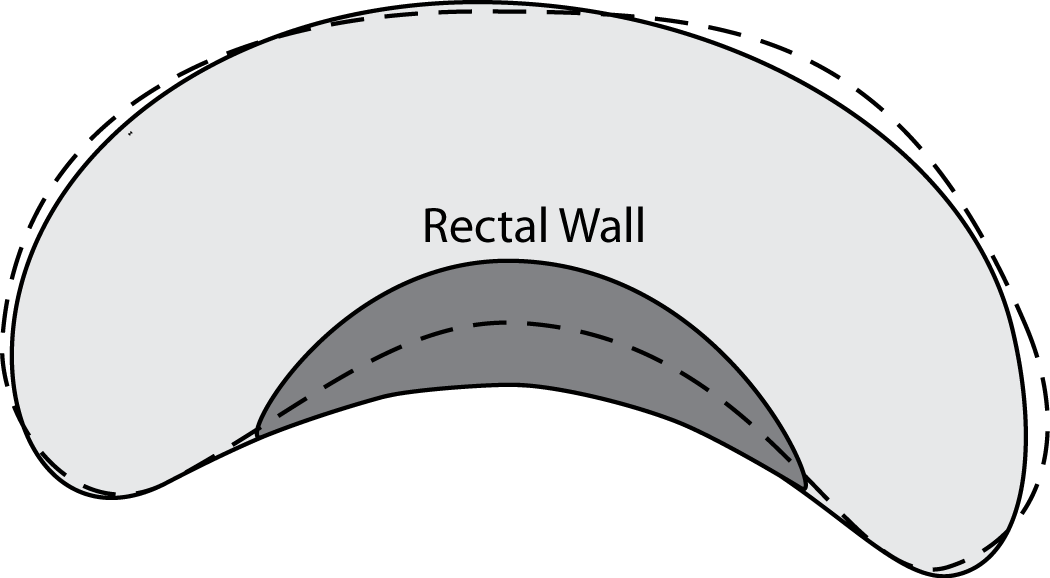

Extracting the Master Shape (Algorithm 1) – In order to calculate the extended accuracy measures, one apparently needs a very different approach to segmentation evaluation. Using existing ground-truth images , we calculate a general (master) shape . In addition to a desired minimum accuracy , the expert has to determine the number of zones . As well, the threshold needs to be set which determines the consensus level for thresholding the accumulated ground-truths (line 3, Algorithm 1) (all pixels with at least overlap among segments will belong to the consensus segment). One may use algorithms like STAPLE [9], however this failed in working with a large number of segments in our experiments such that we we were forced to use our simple method to extract the master shape .

Creating the Master Gold (Algorithm 2) – In a second phase, one would need to let the expert delineate zones in the master shape using points (clicks) per zone to create the master gold . We implemented Algorithm 2 to perform this phase, however, the zones can be delineated using any available image editor. Also one has to bear in mind that the creation of the master gold is a one-time task and generally does not need to be repeated.

A soon as a master gold is available, one can start calculating the accuracy of segments using the ground-truths provided the zones depicted in can be aligned with corresponding points in the -the ground-truth and the segment . Whereas the master gold is one image and universally available for all images, every image with the segment has, as usual, its own ground-truth for evaluation or training purposes.

Mapping instead of Registration (Algorithm 3) – Finding the correspondent pixels in and consequently in , given the zonal coordinates in , seems to be a typical “registration” task. However, based on our experimental results we decided to not use registration algorithms for this purpose. The non-rigid registrations we tested were both time-consuming (which may not be a critical drawback) and inaccurate. Whereas one may use a specific registration algorithm in context of a familiar segmentation task, we do provide a quasi-non-rigid mapping procedure that is very fast, due to its simplicity, and can handle small irregularities quite easily. For this, first we do fix some points on the contour of the master gold (see Algorithm 4 in Appendix) and then map them to the ground-truth (see Algorithm 5 in Appendix) and segment (Algorithm 3; see Figure 3).